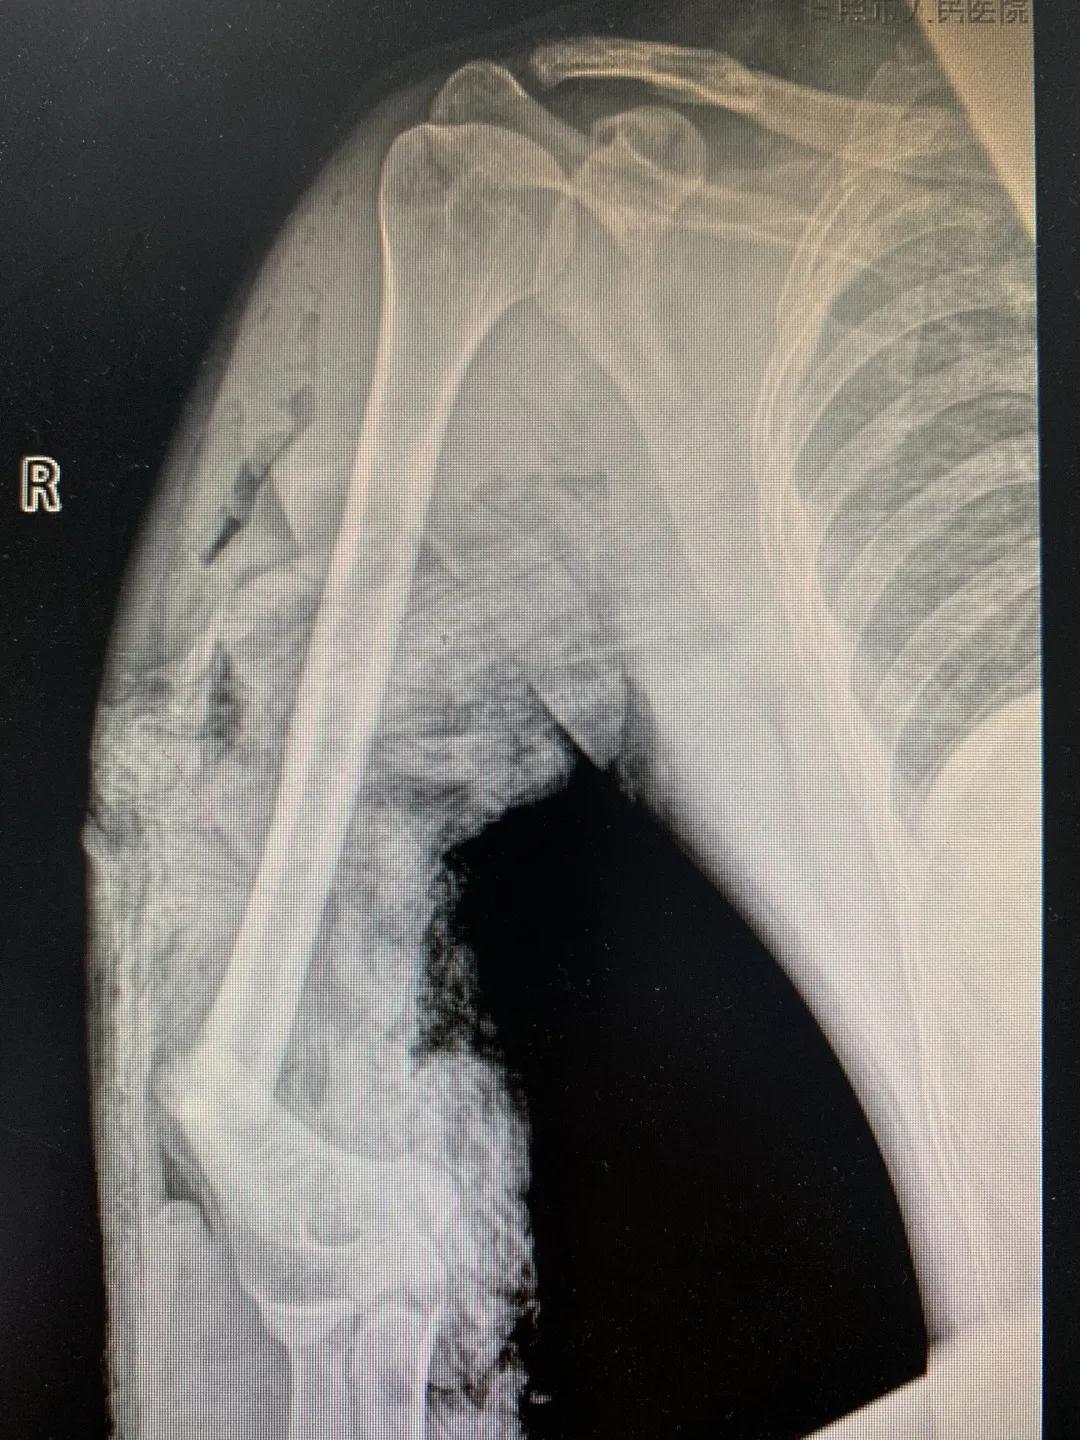

“正常的肢体都有皮肤保护着,如果没有皮肤,我们的肌肉、血管、神经、骨骼露在外面,都会发生坏死。”苑芳昌介绍,伤者的情况非常复杂,伴有多发骨折、肱骨骨折、骨关节的多发错位,还有腕部的骨折,更有血管、神经损伤。不仅如此,伤者右臂在机器里面受到绞伤,肌肉也已经大面积挫伤,各种复杂情形交织在一起甚至让手术“无从下手”。